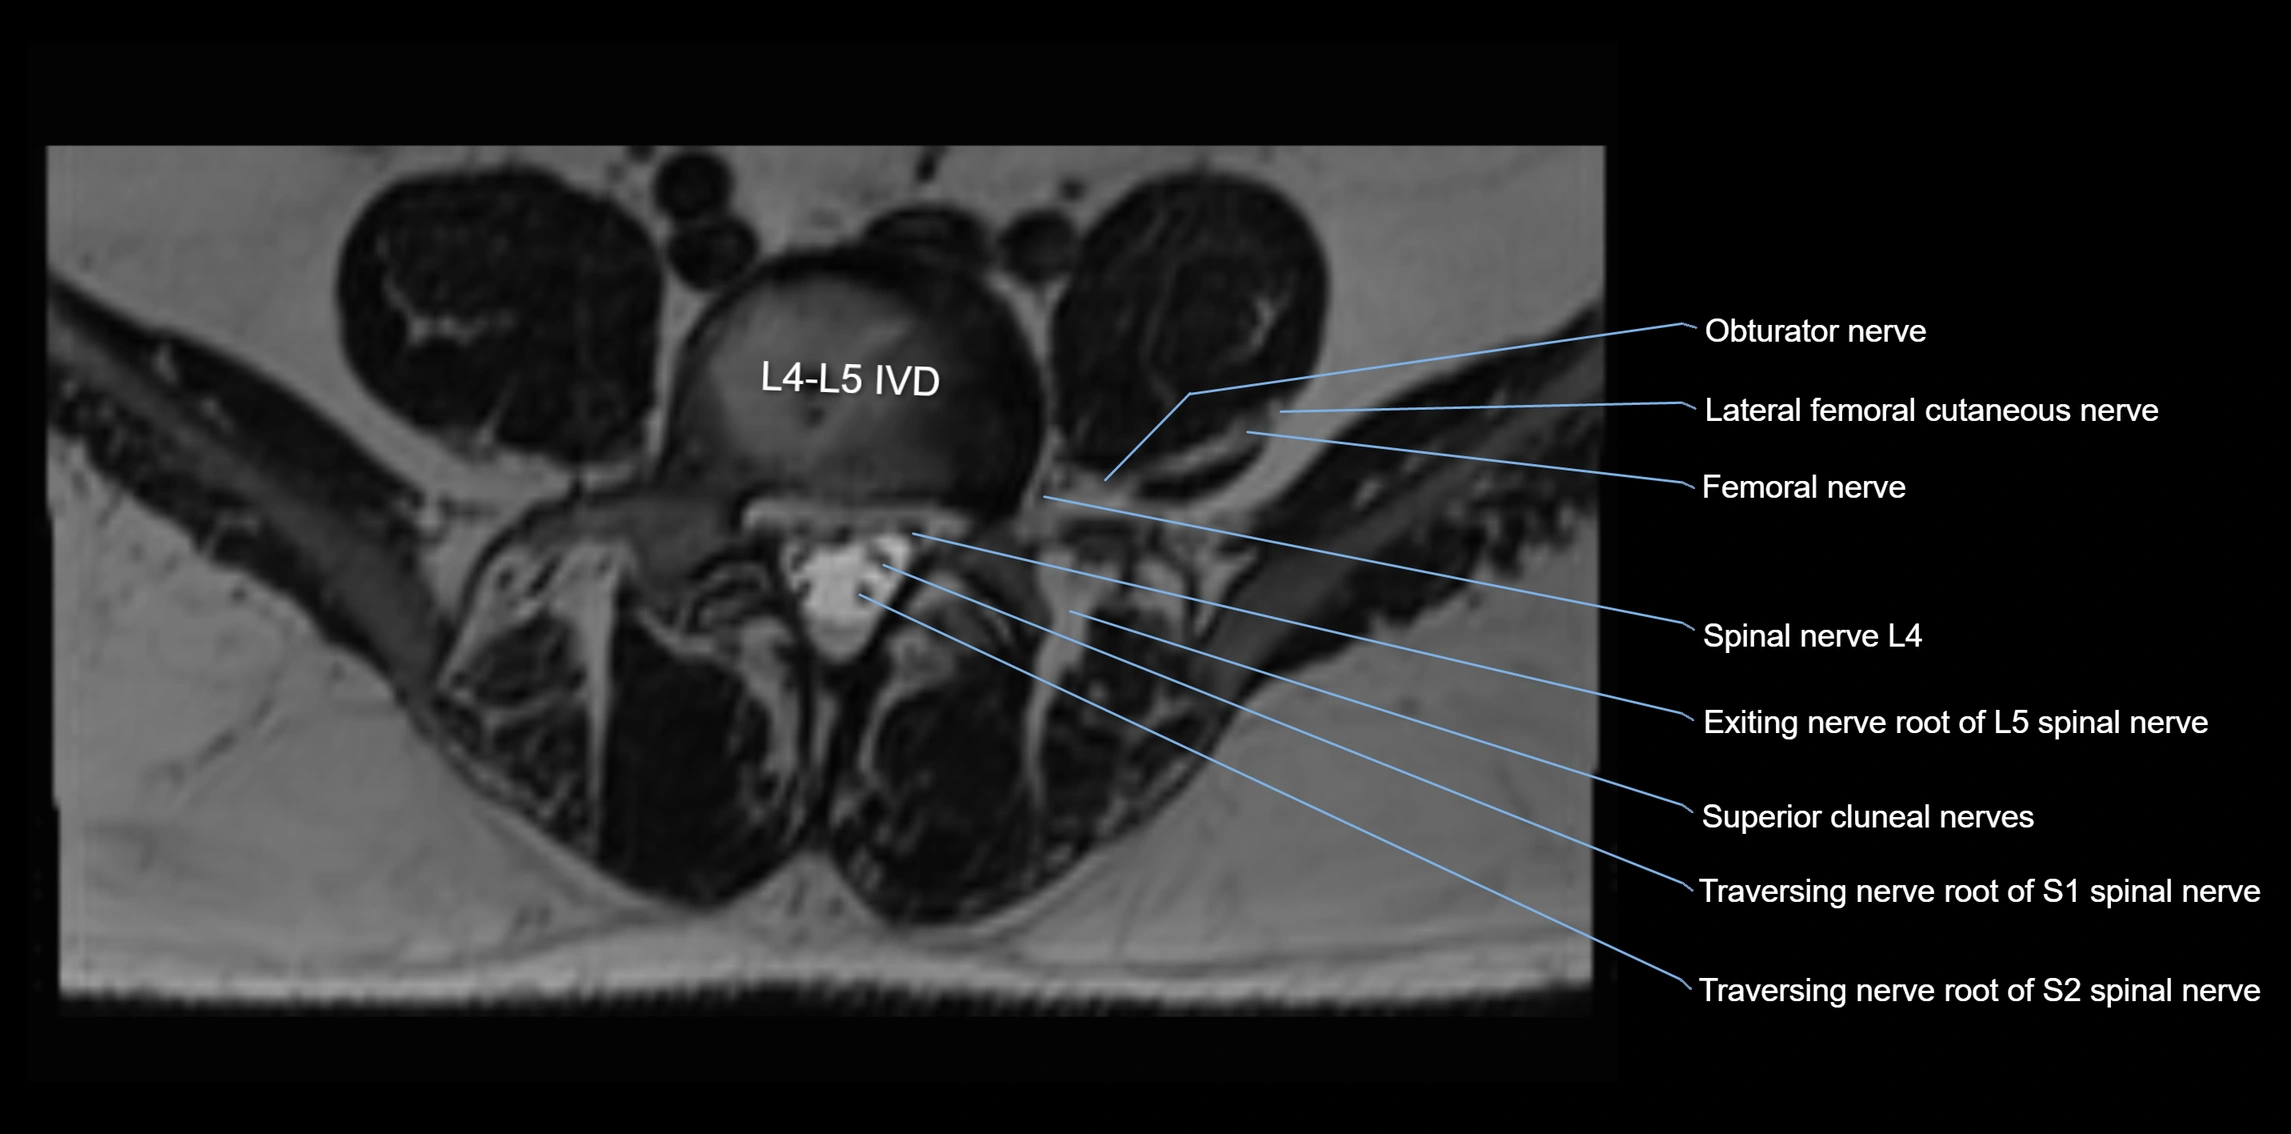

MRI image

image